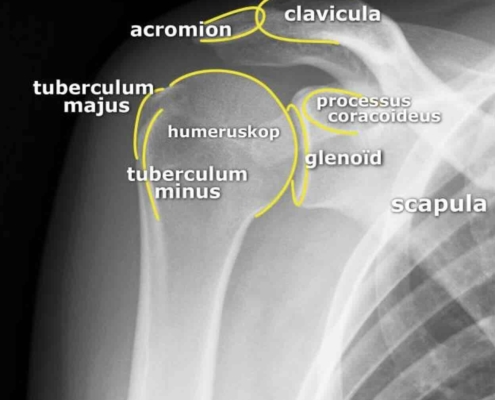

Een frozen shoulder zelf is niet zichtbaar op een röntgenfoto. Pezen en kapsel zijn weke delen die een röntgenfoto niet toont.

Toch vragen we regelmatig een röntgenfoto aan. Niet voor het kapsel, maar voor de botstructuur eromheen.

Wat een röntgenfoto wél toont

• Gewrichtsspleet: bij artrose is deze versmald

• Botuitsteeksels (osteofyten): wijzen op slijtage

• Botverdichting (sclerose): teken van gevorderde artrose

• Kalkafzettingen: bij tendinitis calcarea

• Andere botaandoeningen: breuken of botnecrose

röntgenfoto van een normale schouder

Wanneer vragen we een röntgenfoto aan?

• Bij patiënten boven de 50 jaar met schouderklachten

• Bij vermoeden van artrose naast of in plaats van frozen shoulder

• Wanneer echo en lichamelijk onderzoek geen eenduidige diagnose geven

💡 Bij Orthozorg: Röntgen toont de botstructuur, echo toont het kapsel. Samen geven ze het complete beeld.